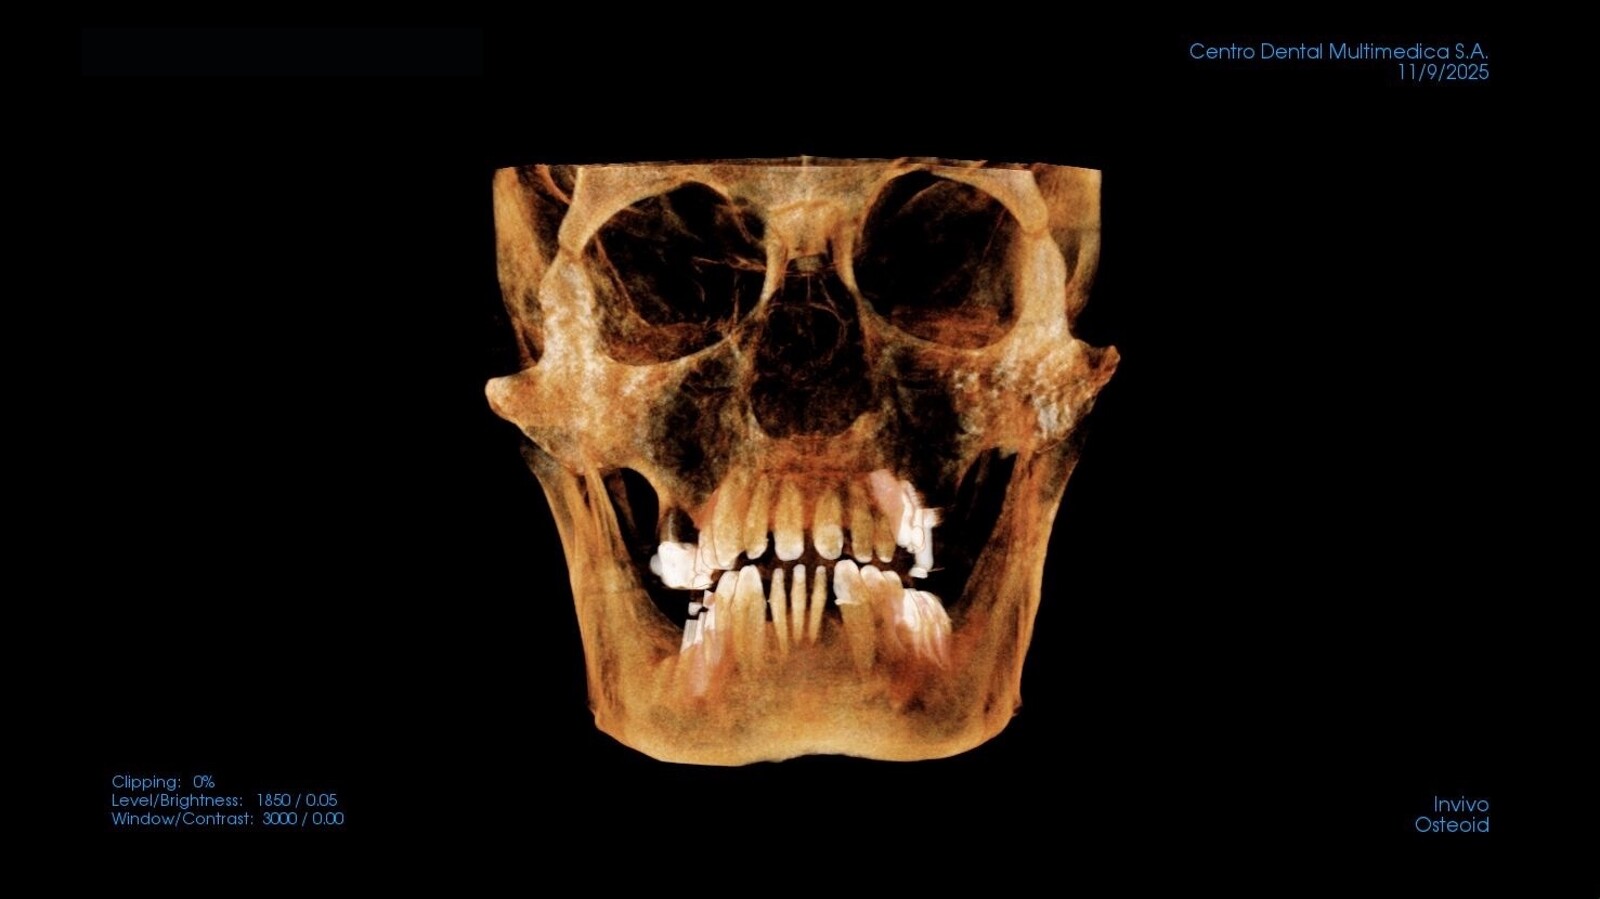

Reconstrucción digital de una tomografía dental en formato de 12 x 18.

Radiografía digital tridimensional

La radiografía digital tridimensional (CBCT) aporta información volumétrica ósea indispensable para la planificación implantológica, quirúrgica y ortodóncica avanzada. Su integración con modelos digitales permite una evaluación tridimensional más precisa de las relaciones anatómicas5.

Reconstrucción de una tomografía del maxilar superior.